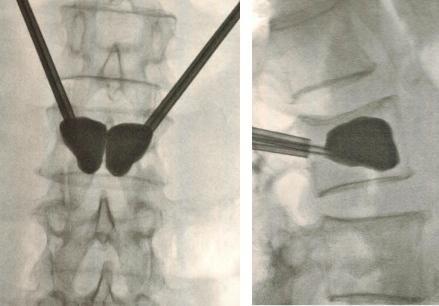

- Inserção das Cânulas: duas agulhas são inseridas através da pele, guiadas por fluoroscopia (raio-X em tempo real), ultrapassando os pedículos vertebrais até o corpo vertebral fraturado.

CIFOPLASTIA: RAIO-X EM TEMPO REAL